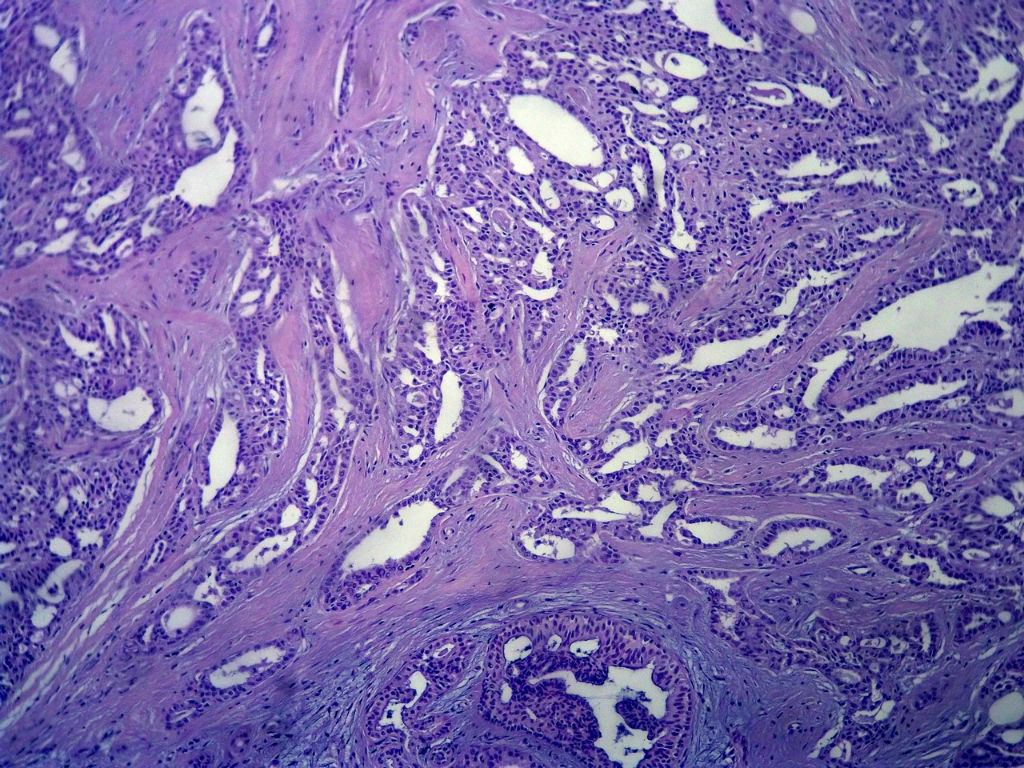

B3806腺病?癌?其他?(12楼常规,24楼免疫组化及会诊结果)

今天的一例术中冰冻。女,49岁,乳腺肿块。人气不旺,换个标题

标签:浸润性导管癌 分泌癌 硬化性腺病

乳腺分泌型癌

1. Most likely no invasive cancer

2 Sclerosing adenosis

3 Ductal epithelial hyperplasia

4. Bundles d Smooth muscle?

导管是乎可见双层上皮,部分上皮增生并有一定异型,考虑硬化性腺病,待石蜡。

导管可见双层上皮,部分上皮增生并有一定异型,考虑硬化性腺病

腺体与腺体之间的对比差异太大,不放心,不除外是癌,如果是我的病例,再次取材冰冻

浸润性导管癌。冰冻切片的诊断是很困难,直接诊断癌风险很大,但是在明显正常的导管间这种成片、成巢有腔的细胞团块也不是良性的表现,有的还似乎有围绕正常导管生长的倾向。诊断ADH还可以,但是不能归到任何一种DCIS的生长方式里。这例值得我好好学习。